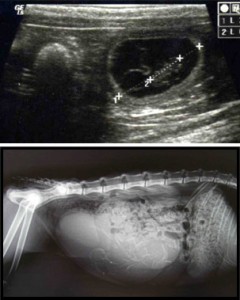

-en cas de disproportion foeto maternelle : représente les principales indications de la césarienne

-elle se rencontre fréquemment chez les races brachycéphales, en effet les tête large écrasées ont du mal à s’engager dans le bassin et sont souvent à l’origine d’une présentation de latéral tête plié sur le cou.

– lors de dépassement du terme ou lorsque la portée ne contient un ou deux chiots

: la taille des foetus devient alors excessive par rapport au diamètre de la filière pelvienne.